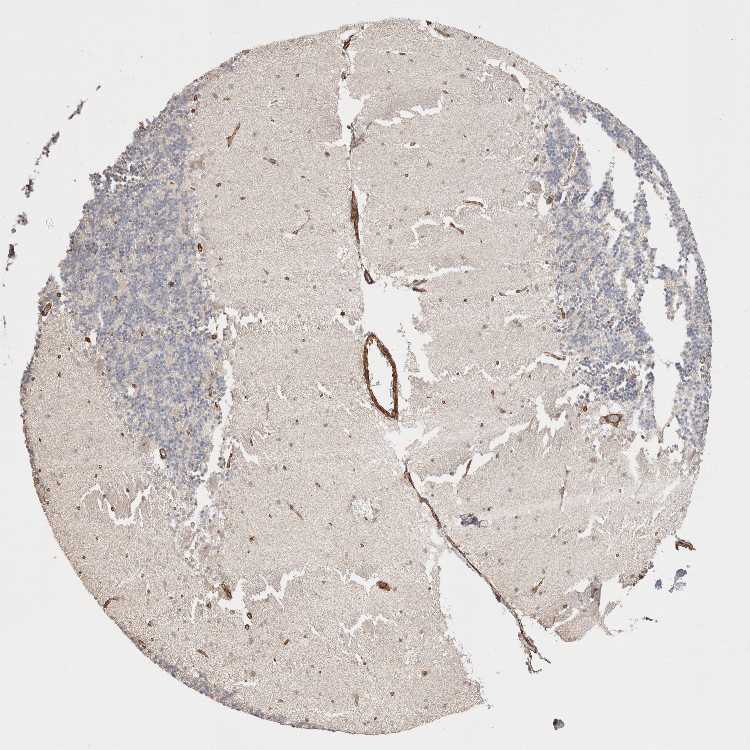

CEREBELLUM - Antibody stainingi

Antibody staining in the annotated cell types in the current human tissue is reported as not detected, low, medium, or high, based on conventional immunohistochemistry profiling in selected tissues. This score is based on the combination of the staining intensity and fraction of stained cells.

Each image is clickable and will lead to virtual microscopy that enables deeper exploration of all samples and also displays staining intensity scores, fraction scores and subcellular localization as well as patient and tissue information for each sample.

Antibody HPA020404Antibody HPA024029Antibody HPA024100

Purkinje cells HighMediumNot detected

Cells in granular layer HighLowNot detected

Cells in molecular layer HighLowNot detected